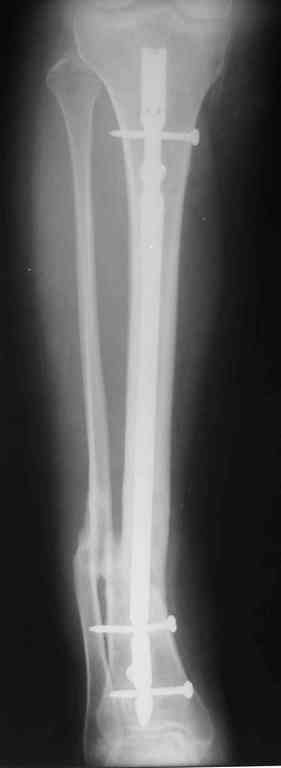

Re: Ложный сустав голени перелом штифта

Прилагаются.

Да , обсуждалась и оптимальным штифтом был выбран " Мастер" Остеомед 10 мм и винты 5 мм, но увы все наши благие намерения разбились о нашу действительность и материальные возможности больной, обращение ее в страховую компанию и т.д., вообщем выкручивались из внутренних резервов, а они были такими 9 мм штифт Остеомед, под 4 мм винты. Ограничили нагрузку. Ошиблись еще и с оценкой сращения, дали полную нагрузку+ больная поправилась на 18 кг, и вот теперь имеем , что имеем.

Действитльность и возвожности остались прежнее, во внутренних резервах есть 11 мм стержень универсальный ( реконструктивный) "Деост-CHM" много спиц и аппарат + ось конечности и отломок штифта и надежда на Ваши советы.